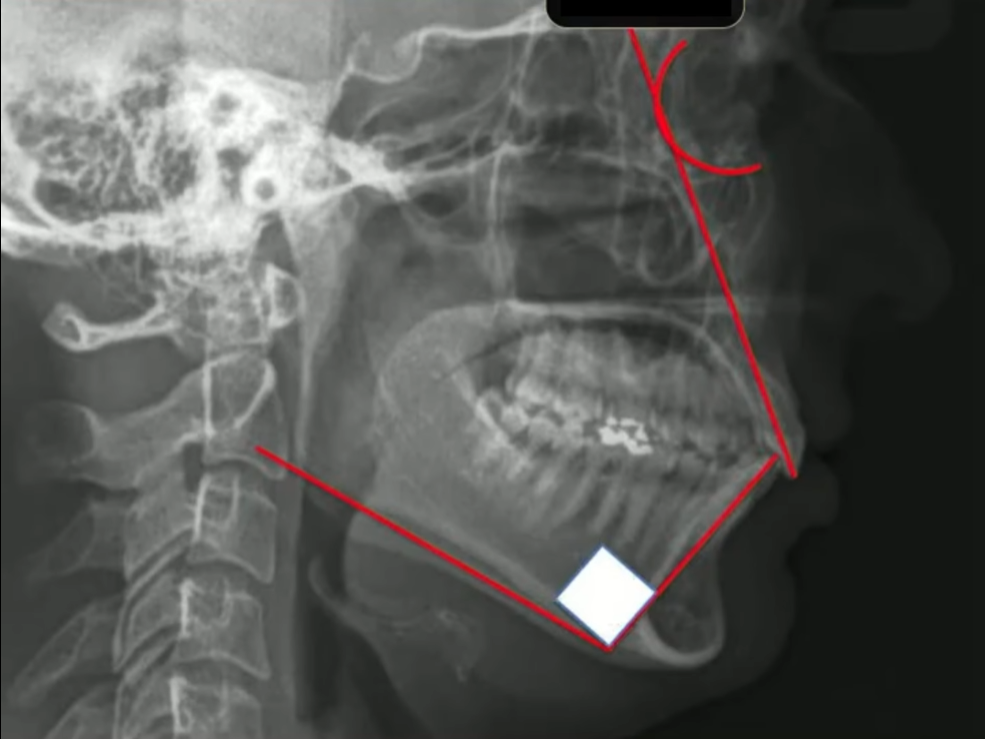

Para eu conseguir isso aqui nessa paciente dessa telerradiografia, obrigatoriamente eu tenho que fazer 4 extrações nessa paciente que eu mostrei para vocês.

Essas fotos aqui são o antes e o depois, então aqui nós tínhamos a paciente biprotrusa e depois das 4 extrações ela ficou com os incisivos bem posicionados:

Vejam a mudança que aconteceu

Se vocês observarem, aqui o longo eixo do incisivo, aqui o longo eixo do incisivo agora está tangenciando a órbita, e aqui o longo eixo do incisivo inferior está mais ou menos com 90 graus com a base da mandíbula: